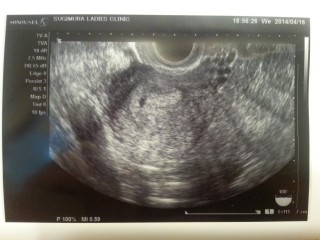

胎嚢2cm!右にズーム画像つけてくれました。

ちゃんと子宮に着床してるね~おめでとう。

でもここからが色々大変だからね!

と、釘を刺されました(^◇^;)

確かに~

また2w後に確認です。心音聴けるといいなぁ~(≧∇≦)